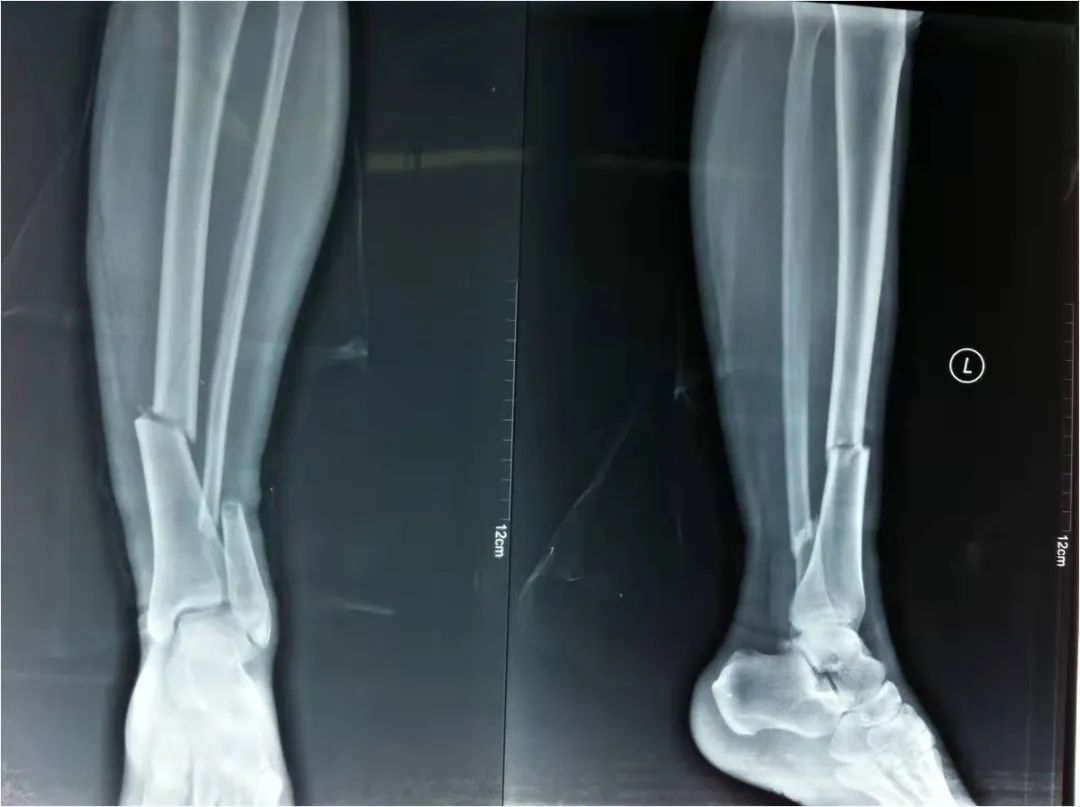

2022年4月22日,我院急救中心接診了一名骨折患者:患者在家不慎摔倒,導(dǎo)致剛做完手術(shù)沒多久的脛腓骨再次受創(chuàng),疼痛劇烈傷情加重。骨科呂國福主任迅速給予夾板外固定治療,并給予止疼治療減輕患者疼痛。經(jīng)診斷患者脛腓骨粉碎性骨折明確,且第一次接骨板釘?shù)廊钥梢?,如不及時(shí)手術(shù)可能出現(xiàn)骨斷端外露發(fā)展為開放性骨折,可能出現(xiàn)骨筋膜室綜合癥。

如采用傳統(tǒng)手術(shù)需大范圍剝離軟組織,手術(shù)切口在18公分,損傷面大,影響骨折愈合。經(jīng)過科內(nèi)術(shù)前討論后與患者及家屬溝通后,呂國福主任決定行小切口微創(chuàng)鈦板植入內(nèi)固定手術(shù)治療,術(shù)中植入內(nèi)固定物并剝離軟組織,此方法對(duì)周圍皮膚破壞小,手術(shù)切口最小僅0.5公分,極大降低皮膚壞死及后期出現(xiàn)骨不連發(fā)生幾率,從而達(dá)到解剖復(fù)位。